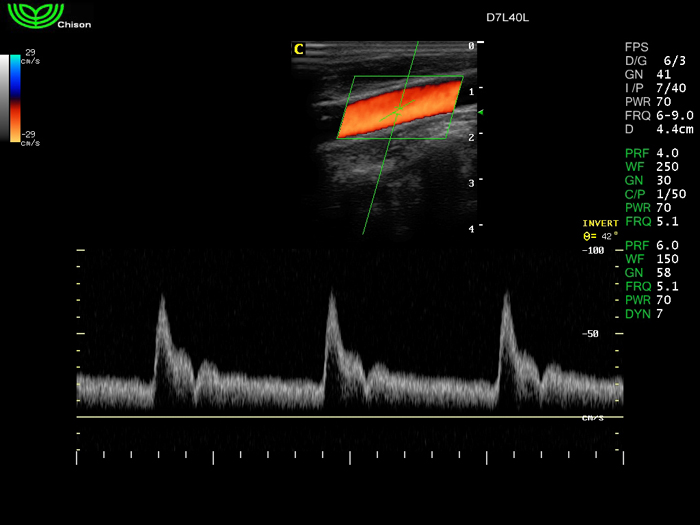

D7L40L 7.5МГц, линейный.

4.0МГц – 13.0 МГц. Применения: грудь, малые органы, нервы, сосуды, венозная катетеризация, мышцы и скелет, управление биопсией. |